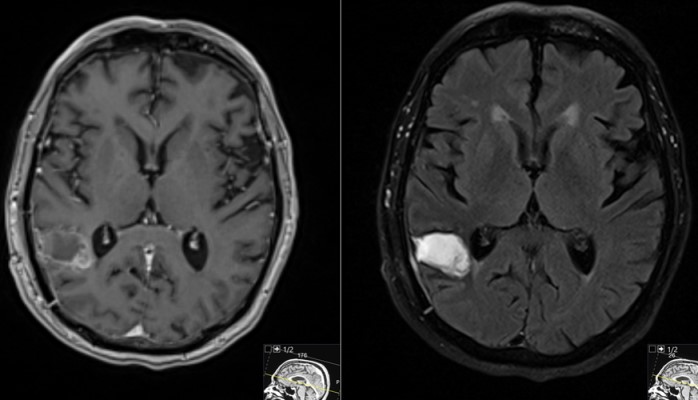

This is a 69 year old male with a known history of renal cell carcinoma who presented with cognitive decline and a neck mass.He had memory issues which were attributed to chemotherapy. He also was having new headaches. The neck mass was due to an infection. Neurologic examination was relatively unremarkable.